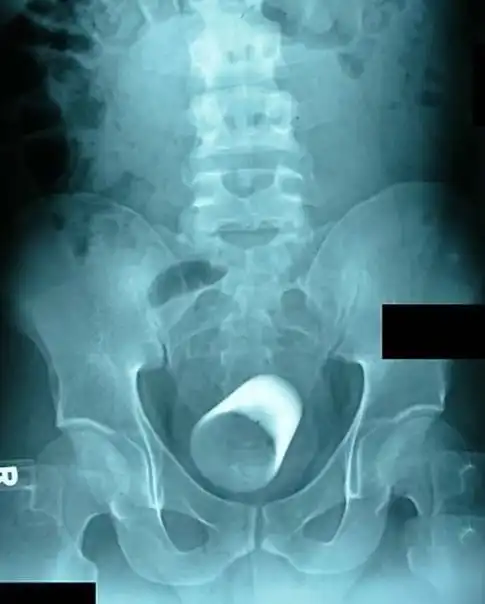

Стопка для шотов. В анусе.